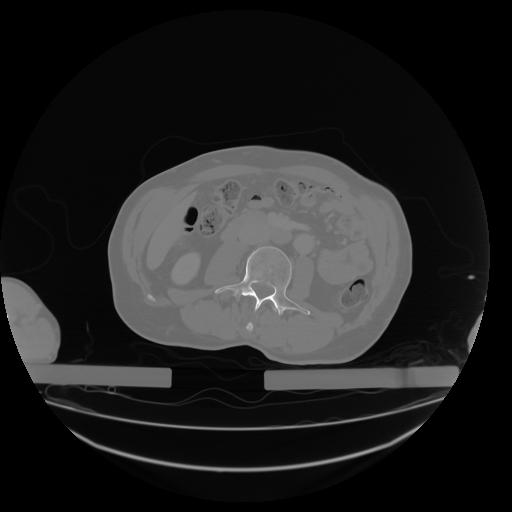

27 CUERPO,CE,Axial,3.0,CUERPO,,